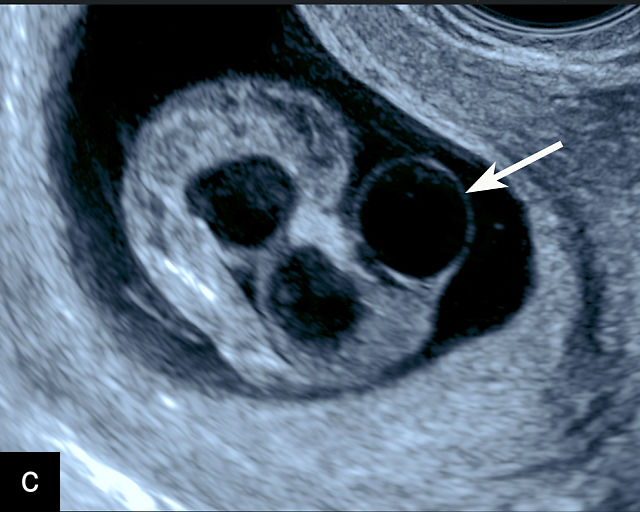

Vasa previa

Vasa previa refers to unprotected fetal vessels running through the membranes over the cervix.30,50,252,253 These vessels often rupture when the membranes rupture during labor or in late pregnancy, resulting in fetal hemorrhage and often exsanguination.252 As a result, this condition is associated with high perinatal mortality.35,252 A large study found a 56% perinatal mortality when vasa previa was not diagnosed prenatally.35 Prenatal diagnosis with ultrasound and cesarean delivery before labor or rupture of the membranes prevents this high perinatal mortality.254,255,256 Risk factors for vasa previa include second-trimester placenta previa or low-lying placenta, velamentous cord insertion, pregnancy resulting from in-vitro fertilization, multifetal gestation and placenta with accessory lobe.30,36,50,257,258,259,260,261

There are three types of vasa previa.30,262 In Type 1, the cord inserts into the membranes rather than the placenta. Unprotected vessels then traverse the membranes over the cervix to insert into the placenta (Figure 21a; Video 12). In Type 2, unprotected vessels running through the membranes over the cervix connect the main placental lobe with an accessory lobe (Figure 21b).263 In Type 3, there is generally a normal placental cord insertion, and unprotected vessels exit one placental edge, run through the membranes over the cervix and then boomerang to insert into the placental edge at another site (Figure 21c).25,28,29,264 Regardless of the type, all these expose the fetus to the same risks.